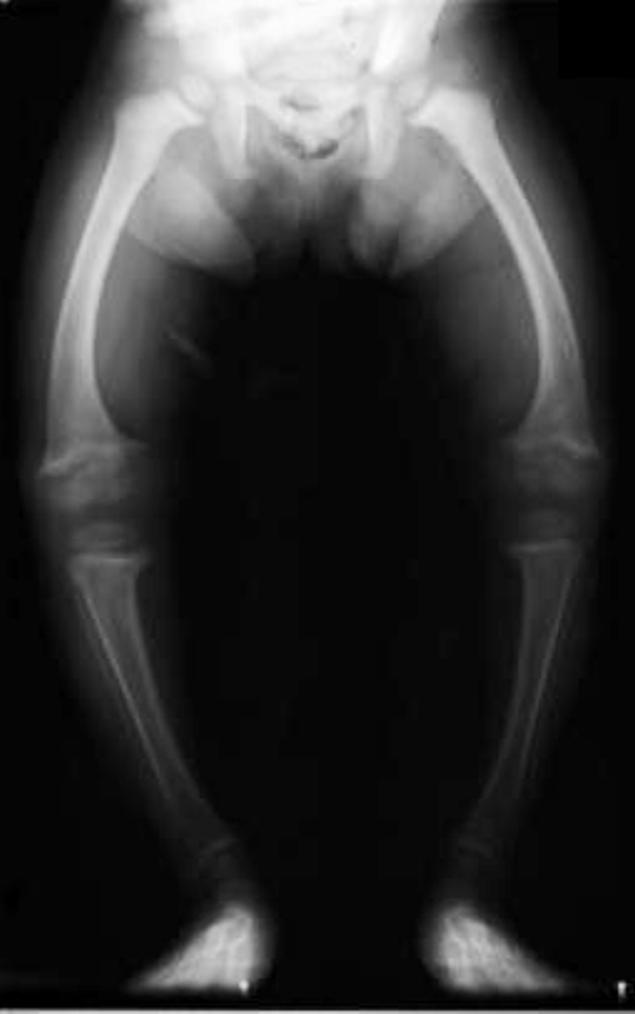

O a doua boală a cărei recrudescenţă îi îngrijorează pe medici este rahitismul, tot o boală carenţială, datotrată lipsei de calciu şi/sau vitamina D. Am scris şi/sau deaorece există cazuri în care calciul, altminteri existent în cantitate suficientă în dietă, nu este utilizat corespunzător de către organism din cauza lipsei vitamimei D. Vitamina este neapărat necesarpă pentru fixarea calciului în oase, aşadar pentru mineralizarea corespunzătoare şi dezvoltarea normală a scheletului. În cazul unei deficienţe de absorbţie şi fixare a calciului în ţesutul osos, oasele copiilor cresc defectuos, nu au densitatea corspunzătoare („sunt moi”, cum se zice), şi, în cursul creşterii, în loc să se dezvolte în formele armonioase ale unui corp sănătos, suferă felurite deformări care îi spun unui medic competent că acel copil a prezintă o proastă mineralizare a oaselor.

Exact acest lucru se întâmpla în secolul al XIX-lea şi începutul secolului XX în Londra, de pildă, vestită pe atunci pentru aerul îmbâcsit de la periferiile industriale în care locuiau cei săraci: mahalale lugubre, sordide, prin care mişunau copii palizi, malnutriţi, nu rareori cu membrele şi trunchiul deformate de rahitism. Peste trei sferturi din copii din oraşele industriale sufereau de această maladie, considerată pe atunci o boală a sărăciei.

Unul dintre medicii care se declară şocaţi de fenomen este un specialist britanic, Nicholas Clarke, chirurg ortoped la spitalul Southampton General. El şi colegii săi au studiat recent 200 de copii care aveau probleme la nivelul oaselor şi au constatat că 40 dintre ei aveau rahitism în toată regula. 40 din 200! Asta înseamnă 20%, o cincime dintre ei! Orice s-ar spune, e într-adevăr surprinzător (şocant, vorba doctorului Clarke) să vezi aşa ceva într-o ţară dezvoltată ca Marea Britanie (mai ales că respectivii copilaşi crescuseră în sudul ţării, unde, după spusele medicului, e soare suficient).

Dar o explicaţie există: rahitismul nu mai este o boală a sărăciei, aşa cum era acum 100 de ani. Dimpotrivă, acum numeroşi copii din familii cu o situaţie materială bună beneficiază la domiciliu de posibilităţi de distracţie care îi fac să nu-şi mai dorească să iasă din casă, se deplasează cu maşina şi, în general, îşi petrec mult timp în spaţii închise, luminate artificial. Rezultatul: un deficit cronic de vitamina D, manifestat prin rahitism, cu modificări ireversibile ale scheletului.